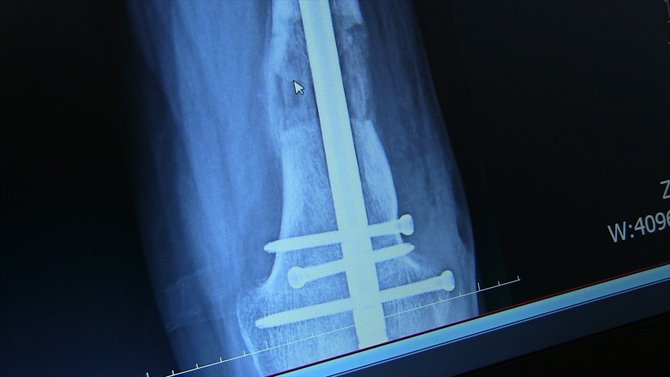

- Platin ve çivilerle ayağındaki kısalık giderildi

Operasyonu gerçekleştiren Farabi Hastanesi Ortopedi ve Travmatoloji Uzmanı Prof. Dr. Mehmet Arazi ise hastanın kendilerine müracaat ettiğinde, sol bacağında ciddi bir kısalık, diz bölgesinde eğrilik ve ayağında fiziksel bozukluk olduğunu söyledi.

Hastanın yaşı ilerledikçe yürüme probleminin arttığını, sol ayağının sadece ayak parmaklarını yere basabildiğini dile getiren Arazi, "Hastamızın, ardışık ameliyatlarla bacağındaki kemikleri uzatabilme, dizindeki ve ayağındaki problemleri giderme kararı aldık. Yaptığımız ameliyatla ilk olarak bacağındaki şekil bozukluğunu düzelttik. Ardından tıbbi olarak kullandığımız çivi ve platinlerle dizin üstündeki ve dizin altındaki kemiği uzattık. Ardından topuk ve ayak bileğindeki bozukluk için de bir operasyon yaptık. Şu anda sağlığı iyi durumda." diye konuştu.